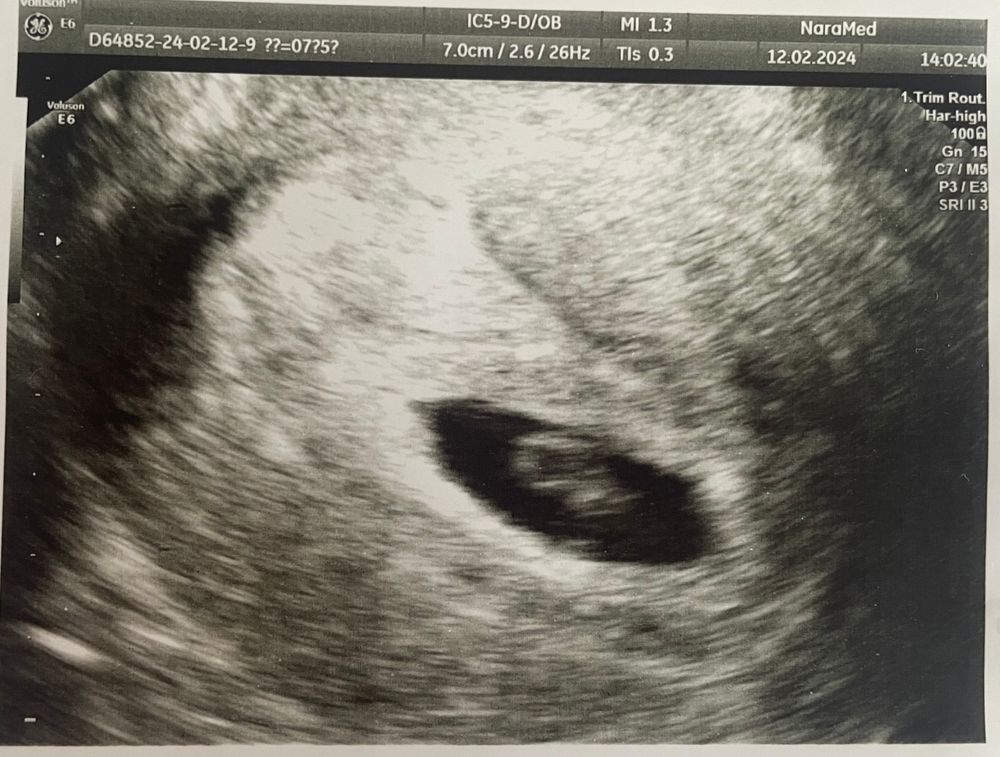

Марина, ну вот 5 числа 3 мм был, а вчера она как-то померила 0.43 см… я и удивилась… но смотрела супер быстро, супер бегло… хотя блин платная клиника… не знаю что делать…

Елена, это вчерашнее УЗИ… ну и заключение выглядит как-то странно… размер ПЯ - это не диаметр, это, судя по всему, в 1 измерении… нет ни размера ЖМ, ни КТР… ничего…

Анастасия , вижу пя 22 мм, ктр 4 мм. С 3 мм до 4 за неделю это плохой рост. Жм визуализируется, не все его замеряют.